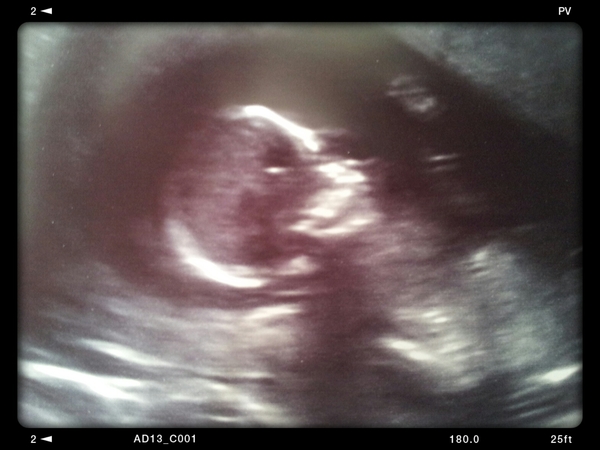

It is real! I didn't imagine it! There is a baby alien in there! I can deep breathe now! And actually catch up/read the thread properly with an iota of concentration!

It's waving! Thank you for all the positive thinking, I'm absolutely sure it worked! Grin Dh is made up, he keeps going "well, this is the best day ever"

starky I'm soooooo chuffed for you I hope you can enjoy it now! And you lucky thing having no symptoms! Grin I'm guessing boy Wink what a beautifully clear scan

Lovely little photo, and so nice to hear how chuffed your DH is. It's actually real now!

Stark that's such a lovely scan, look at baby's little hand! So pleased for you, hopefully it all feels real now.

Great photo Starky! It's properly real now Smile

What a lovely scan Stark! I get so much enjoyment out of OH's excitement.